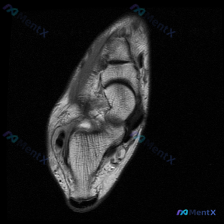

这是一张足踝部T2加权矢状位MRI,显示跟骨、距骨、部分跗骨和足底结构:

- 骨骼:跟骨和距骨骨髓信号基本正常,皮质边缘清晰,未见明显异常信号

- 关节:跟距关节间隙清晰,无明显关节面侵蚀或严重狭窄

- 异常发现:跟骨足底前方、足底筋膜起点处可见片状T2高信号影,位于筋膜附着点周围软组织间隙内,范围局限、边界相对模糊,提示局部液体积聚/水肿,周围软组织层次稍模糊